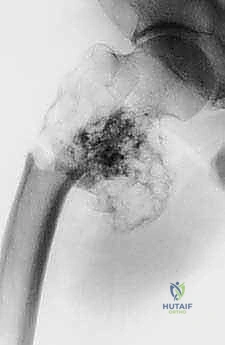

| الأشعة السينية (X-rays) | التقييم الأولي السريع لشكل العظم، اكتشاف الكسور المرضية، وتحديد نمط تدمير العظم. | تعطي الجراح فكرة عامة عن حجم المشكلة وموقعها. |

* الساركوما العظمية (Osteosarcoma): الورم الأكثر شيوعاً، يظهر غالباً في منطقة الركبة (أسفل الفخذ أو أعلى القصبة). يتطلب استئصالاً واسعاً مع هوامش آمنة (إزالة جزء من العظم السليم المحيط بالورم لضمان عدم ترك خلايا سرطانية).

بعض الأورام الحميدة، مثل "الورم ذو الخلايا العملاقة" (Giant Cell Tumor)، رغم أنها لا تنتشر إلى أعضاء أخرى، إلا أنها تنمو بشراسة موضعياً وتدمر المفصل والعظم المحيط به. إذا كان التدمير واسع النطاق، يكون الاستئصال وإعادة البناء هو الحل الأفضل.